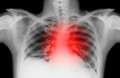

【精彩病例】酷似急性心肌梗死的暴发性心肌炎一例